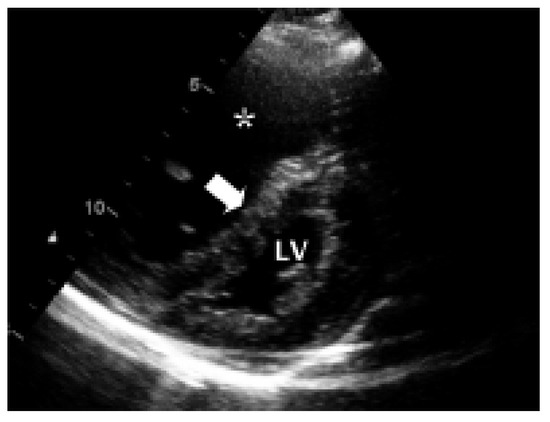

Progrediente Herzinsuffizienz Trotz Biventrikulärer Stimulation

by C. Bösch, B. Schaer and S. Osswald

Drei Monate nach Implantation eines CRTGerätes hatte sich die Dyspnoe des Patienten von NYHA IV auf NYHA II verbessert [...] Full article

Show Figures

Figure 1